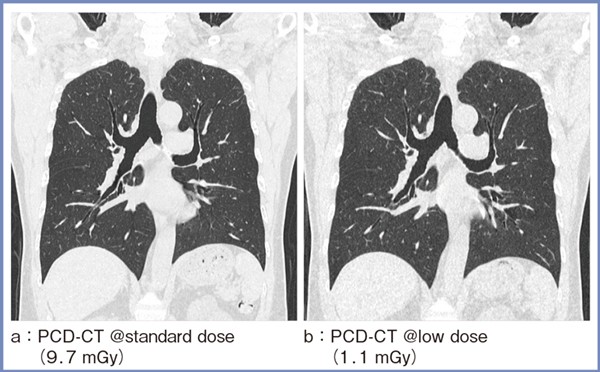

図3はPCD-CTによる肺の画像であるが,線量を1/10に低減しても,遜色なく診断可能な画質が得られている(b)。

図3 PCD-CTによる肺の低線量CT